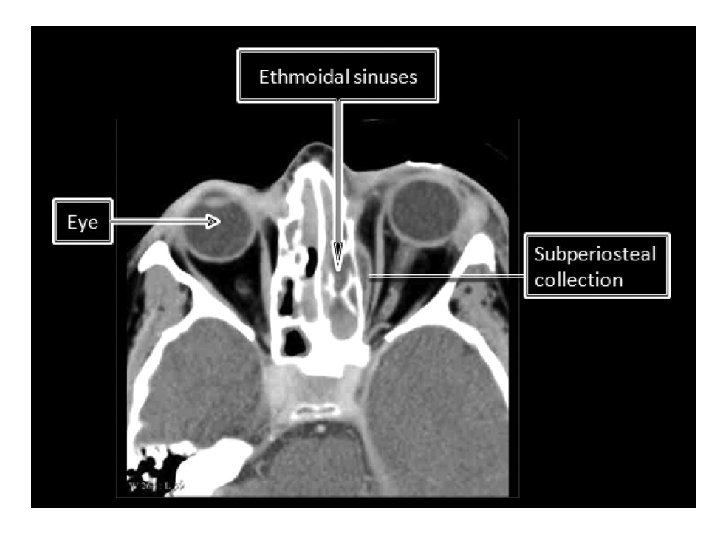

• • Subperiosteal Abscess Pus formation between periorbita and lamina papyracea Displace orbital contents downward and laterally Proptosis, chemosis, ophthalmoplegia Risk for residual visual sequelae May rupture through septum and present in eyelids

Surgical drainage • Worsening visual acuity or extraocular movement • Lack of improvement after 48 hours May be treated medically in 50 -67% • Meta-analysis cure rate 26 -93% • Combined treatment 95 -100%

• Open ethmoids and remove lamina papyracea Approaches • External ethmoidectomy (Lynch • incision)is most preferred • Endoscopic ideal for medial abscesses • Transcaruncular approach • Transconjunctival incision • Extend medially around lacrimal caruncle